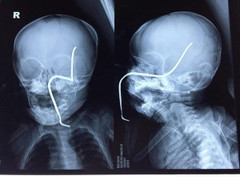

Một bé gái 8 tháng tuổi đến từ Sơn Tây bị một thanh sắt rỉ đâm thủ hộp sọ khi đang chơi đùa.